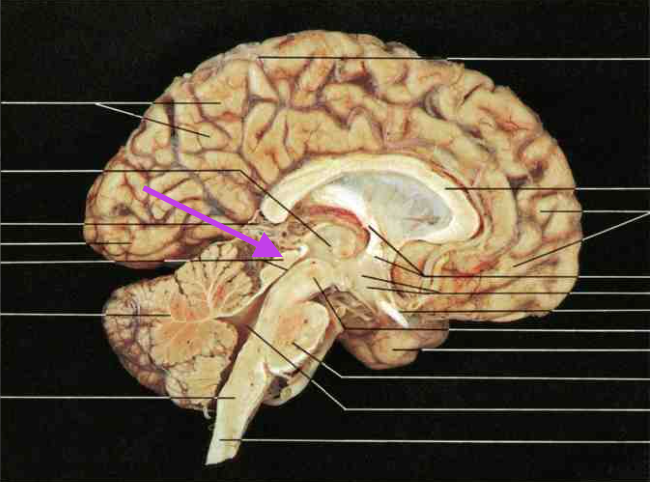

Frontal Lobe. Section is Cerebrum and diencephalon

Central Sulcus. Section is Cerebrum and diencephalon

Parietal Lobe. Section is Cerebrum and diencephalon

Temporal Lobe. Section is Cerebrum and diencephalon

Occipital Lobe. Section is Cerebrum and diencephalon

Lateral Sulcus (fissure). Section is Cerebrum and diencephalon

Longitudinal Fissure. Section is Cerebrum and diencephalon

Precentral Gyrus. Section is Cerebrum and diencephalon

Postcentral Gyrus. Section is Cerebrum and diencephalon

Corpus callosum. Section is Cerebrum and diencephalon

Thalamus and Third Ventricle. Section is Cerebrum and diencephalon

Hypothalamus. Section is Cerebrum and diencephalon

Pineal Body. Section is cerebrum and diencephalon.

Mamillary Bodies. Section is cerebrum and diencephalon.

Interventricular Foramen. Section is cerebrum and diencephalon. Connects the third ventricle to the lateral ventricles.

Lateral Ventricle. Section is cerebrum and diencephalon.